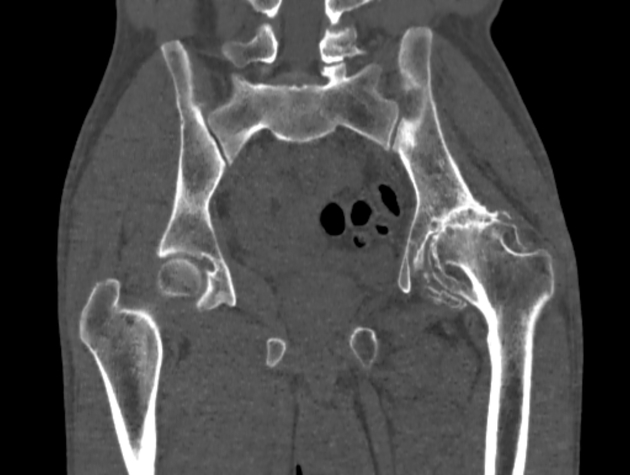

• CT Scan (Computed Tomography): A CT scan provides cross-sectional images of the hip, offering more detail than an X-ray. It can reveal changes in bone density and joint structure.